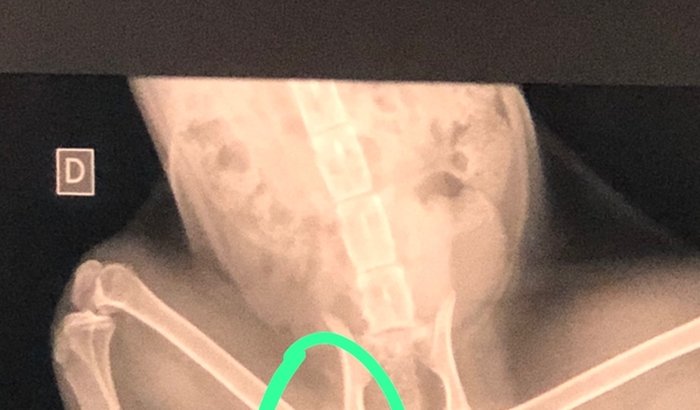

Fumacinha é o nome que demos ao gato que apareceu nas nossas vidas justamente no dia que fazia 2 anos que minha irmã morreu. Minha sobrinha se apegou de uma forma muito profunda a este bichano. A gente se impressionou com a forma como ele se sente a vontade na nossa casa e o quanto ele gosta de ficar deitado em qualquer canto. Ele sempre anda um pouco e depois deita. Então percebemos que Fumacinha veio com uma deficiência. Ele manquejava de uma das patas. No intuito de descobrir o que se passava naquela pata levamos ele ao veterinário. E detectamos a necessidade de fazer uma cirurgia na cabeça do fêmur. O osso está quebrado. Por isso que ele sempre deita. Não resiste a dor. Que dó sentimos aos imaginar a dor que ele está suportamos. Já adquirimos os medicamentos para amenizar a dor e a inflamação, mas precisaremos providenciar a cirurgia. Essa cirurgia que corrigirá este osso quebrado tem o custo de R$1800,00. Se você gosta de animais e quer nos ajudar, por favor, colabore com algum valor aqui na vaquinha ou no pix 317.048.358-79. Obrigado!